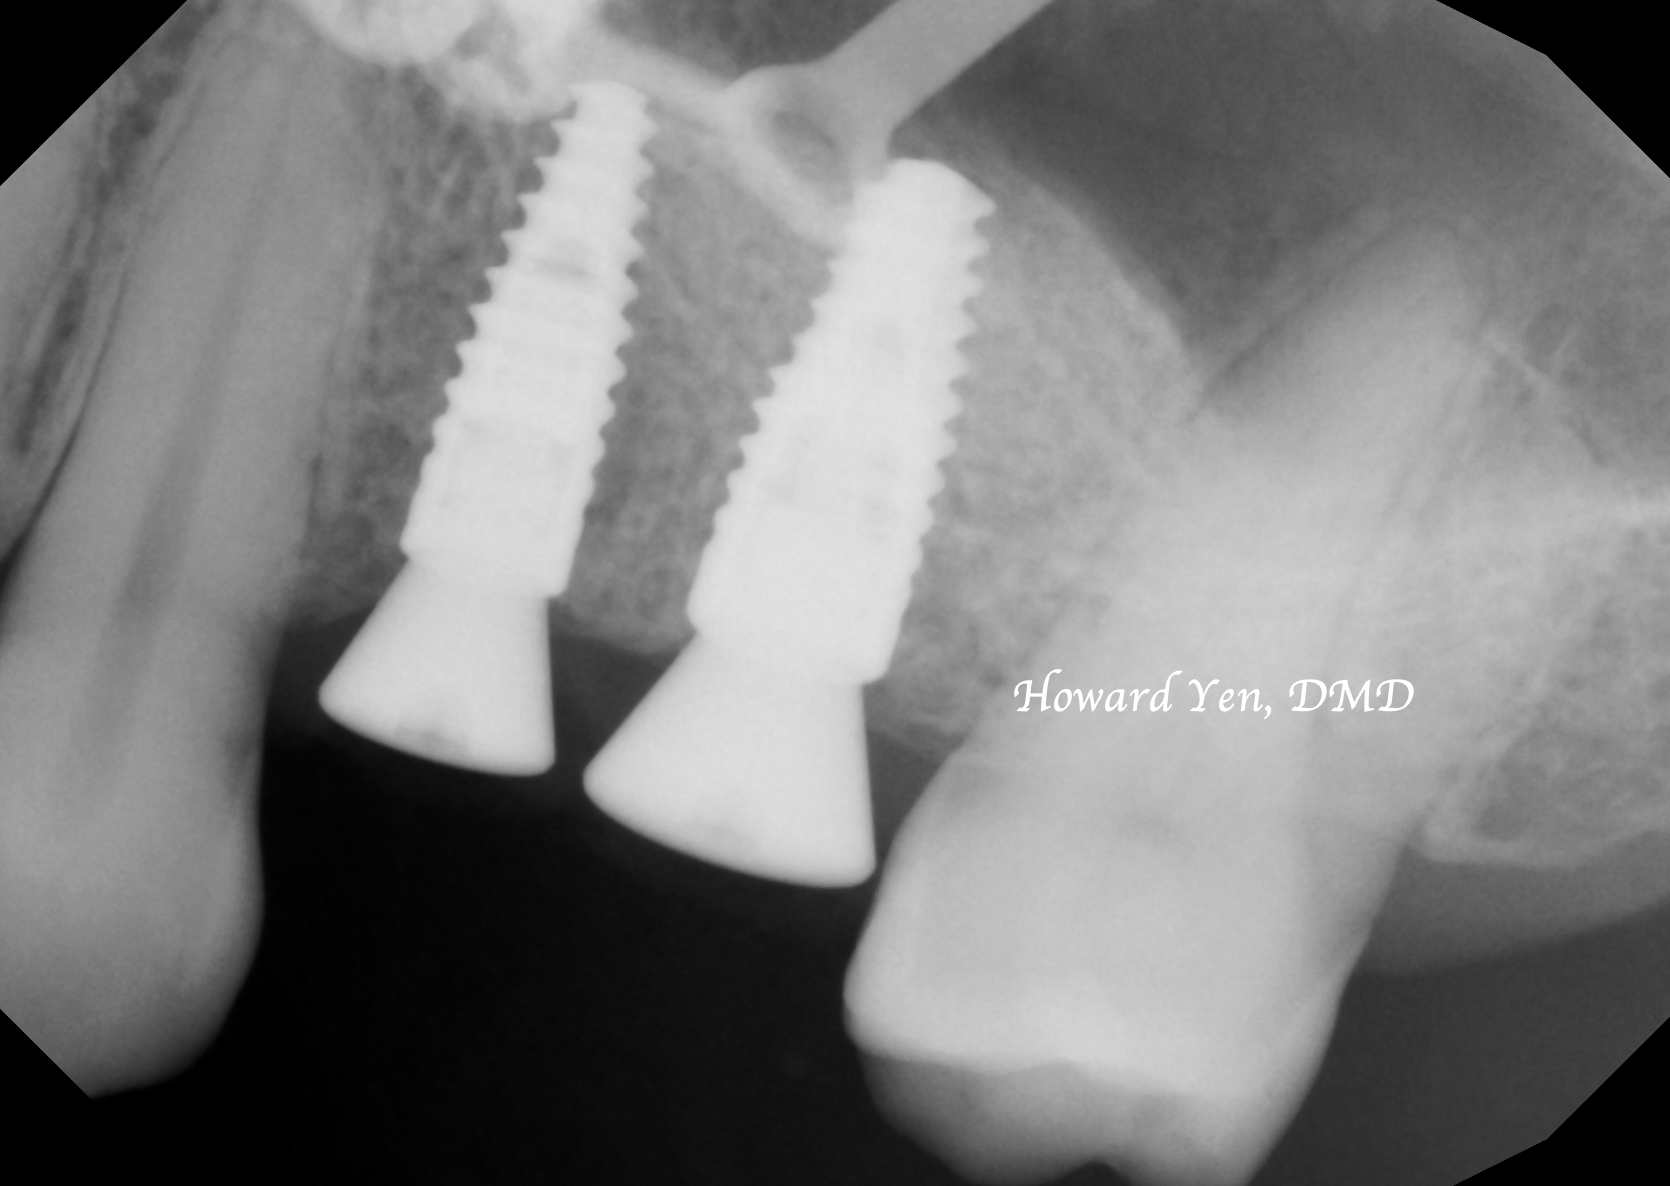

Depending on the amount of bone graft volume needed, dental implant can sometimes be placed simultaneously with sinus lift bone graft to help patient in reducing the overall treatment & healing time.